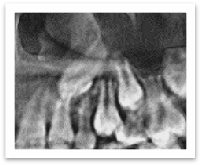

当然,还有一种非常极端的情况就是脱落乳牙对应的恒牙是先天缺失的,根本就没有恒牙的“小种子”,萌出就无从谈起了。

箭头所示恒牙先天缺失